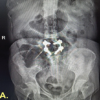

The 8-year-old girl presented with bilateral cleft hands and feet, with complaints of discomfort in wearing shoes (Fig. 1).

Figure 1: (a) 8-year-old girl with bilateral cleft hands; (b) Radiographs of both hands; (c) Function of hands; (d) Bilateral cleft feet; (e) Radiographs of both feet; (f) Bottom view of both feet; (g) Ectodermal dysplasia in the form of peg-shaped incisors.

Clinical description

Her hand function was adequate to meet her daily requirements, with good grasp and apposition of fingertips. Cutaneous examination revealed a keloid over the sternum, sparse scalp hair, and no other significant abnormalities. Oral examination showed peg-shaped incisors with no evidence of cleft lip or palate. Radiographs of both hands showed the absence of central metacarpals bilaterally, with fusion of the middle phalanx and duplication of the distal phalanx of the left hand. Radiographs of both feet showed the absence of the central metatarsals, transverse bones in the depth of the cleft (left), and brachydactyly with a deviated great toe (right). Ultrasound (USG) abdomen and pelvis showed no congenital anomaly.

Management

In view of the good hand function, surgical intervention was not contemplated, and she was advised to undergo 6-monthly follow-up to monitor the progression of her right toe deformity.